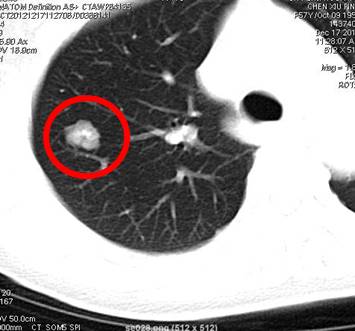

是指肺内直径≤3cm的密度增高影,通俗讲就是CT上黑色的肺里有小白点。>3cm的白色块状影称为肺肿块,通常肿瘤的可能性很大。

结节直径≤3cm

结节直径>3cm